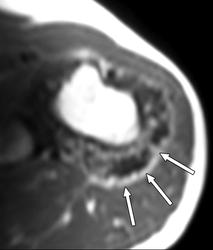

Юкстакортикальная хондросаркома (син.: паростальная хондросаркома, периостальная хондросаркома)—довольно редкая злокачественная опухоль, которая составляет 2 % от общего числа хондросарком. До 80 % больных находятся в возрасте старше 20 лет и лишь 1/3 из них предъявляют жалобы на боль. Опухоль постепенно увеличивается в размерах в течение многих месяцев. Наиболее частая ее локализация — метафизарая часть бедренной кости. Реже поражаются плечевая кость, кости таза, очень редко —ребра и кости стопы. Рентгенологическая картина напоминает то, что характерно для периостальной хондромы с ее блюдцеобразным вдавлением и склерозированным краем в пораженной кости. В некоторых случаях обнаруживается частичное разрушение кортикальной пластинки, и тогда граница опухоли с окружающей костью становится расплывчатой. На границе опухоли с непораженной костью часто видна треугольная склеротическая шпора. Юкстакортикальная хондросаркома часто достигает больших размеров: 7—17 см в диаметре. При осмотре невооруженным глазом юкстакортикальная хондросаркома имеет вид дольчатого новообразования беловато-серого цвета, полупрозрачного на разрезе. На поверхности разреза часто встречается очаговое обызвествление. Подлежащая кортикальная пластинка разрушена и замещена склерозированной костной тканью. Опухоль никогда не проникает в костномозговой канал, хотя под надкостницей она разрастается очень широко.

Под микроскопом отдельные дольки, состоящие из зрелого гиалинового хряща, окружены тонкими фиброзными прослойками, которые местами имеют миксоидный вид, или костными балками (по типу костной метаплазии). Опухолевые клетки лишены способности продуцировать остеоид. Степень злокачественности юкстакортикальной хондросаркомы обычно 1-я или 2-я. Обычно обнаруживается инвазия опухоли в мягкие ткани.

Периостальная хондросаркома встречается очень редко. Она подразделяется на истинно периостальную хондросаркому, когда вся опухоль располагается на наружной и на внутренней поверхностях надкостницы. Опухоли не имеют клинически четкой границы, поэтому при попытках иссечения только участка надкостницы опухоль обычно рецидивирует.

Мы наблюдали женщину 56 лет, которой опытные хирурги иссекали надкостницу с опухолью в нижней трети лучевой кости, и оба раза наступали рецидивы. Нами была произведена резекция нижнего конца обеих костей предплечья с замещением дефекта; хороший эффект отмечен в течение 26 лет. Рецидивы при иссечении надкостницы объясняются, по нашему мнению, тем, что невозможно определить, какую часть окружности кости поразила опухоль и где она проросла в кортикальный слой. Необходима компьютерная томография.